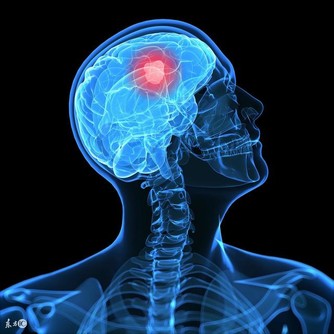

如果放著不管,有些養分和氧氣不能有效到達周邊細胞,就會面臨細胞死亡,而且血液粘稠容易引起血管擁堵,但剛開始發作的時候,並沒有什麼明顯標誌的信號,很容易造成大家的忽視,一般輕者會有頭暈,容易忘東西,腰疼長斑皺紋,失眠,體寒等症狀,嚴重的就會出現動脈硬化,引起心肌梗塞,甚至還會引起腦中風現象。